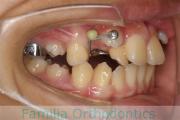

歯並びを治したいということで来院されました。下あごがやや右側に偏位して後退している、上顎前突(出っ歯)でした。上下左右から小臼歯を抜歯して、歯科矯正用アンカースクリューを併用したマルチブラケット法にて治療を行いました。約2年、24回の来院をしていただきました。

下顎の後退はいびきなどの上部気道の障害が出やすいと考えられます。

右側

正面

左側